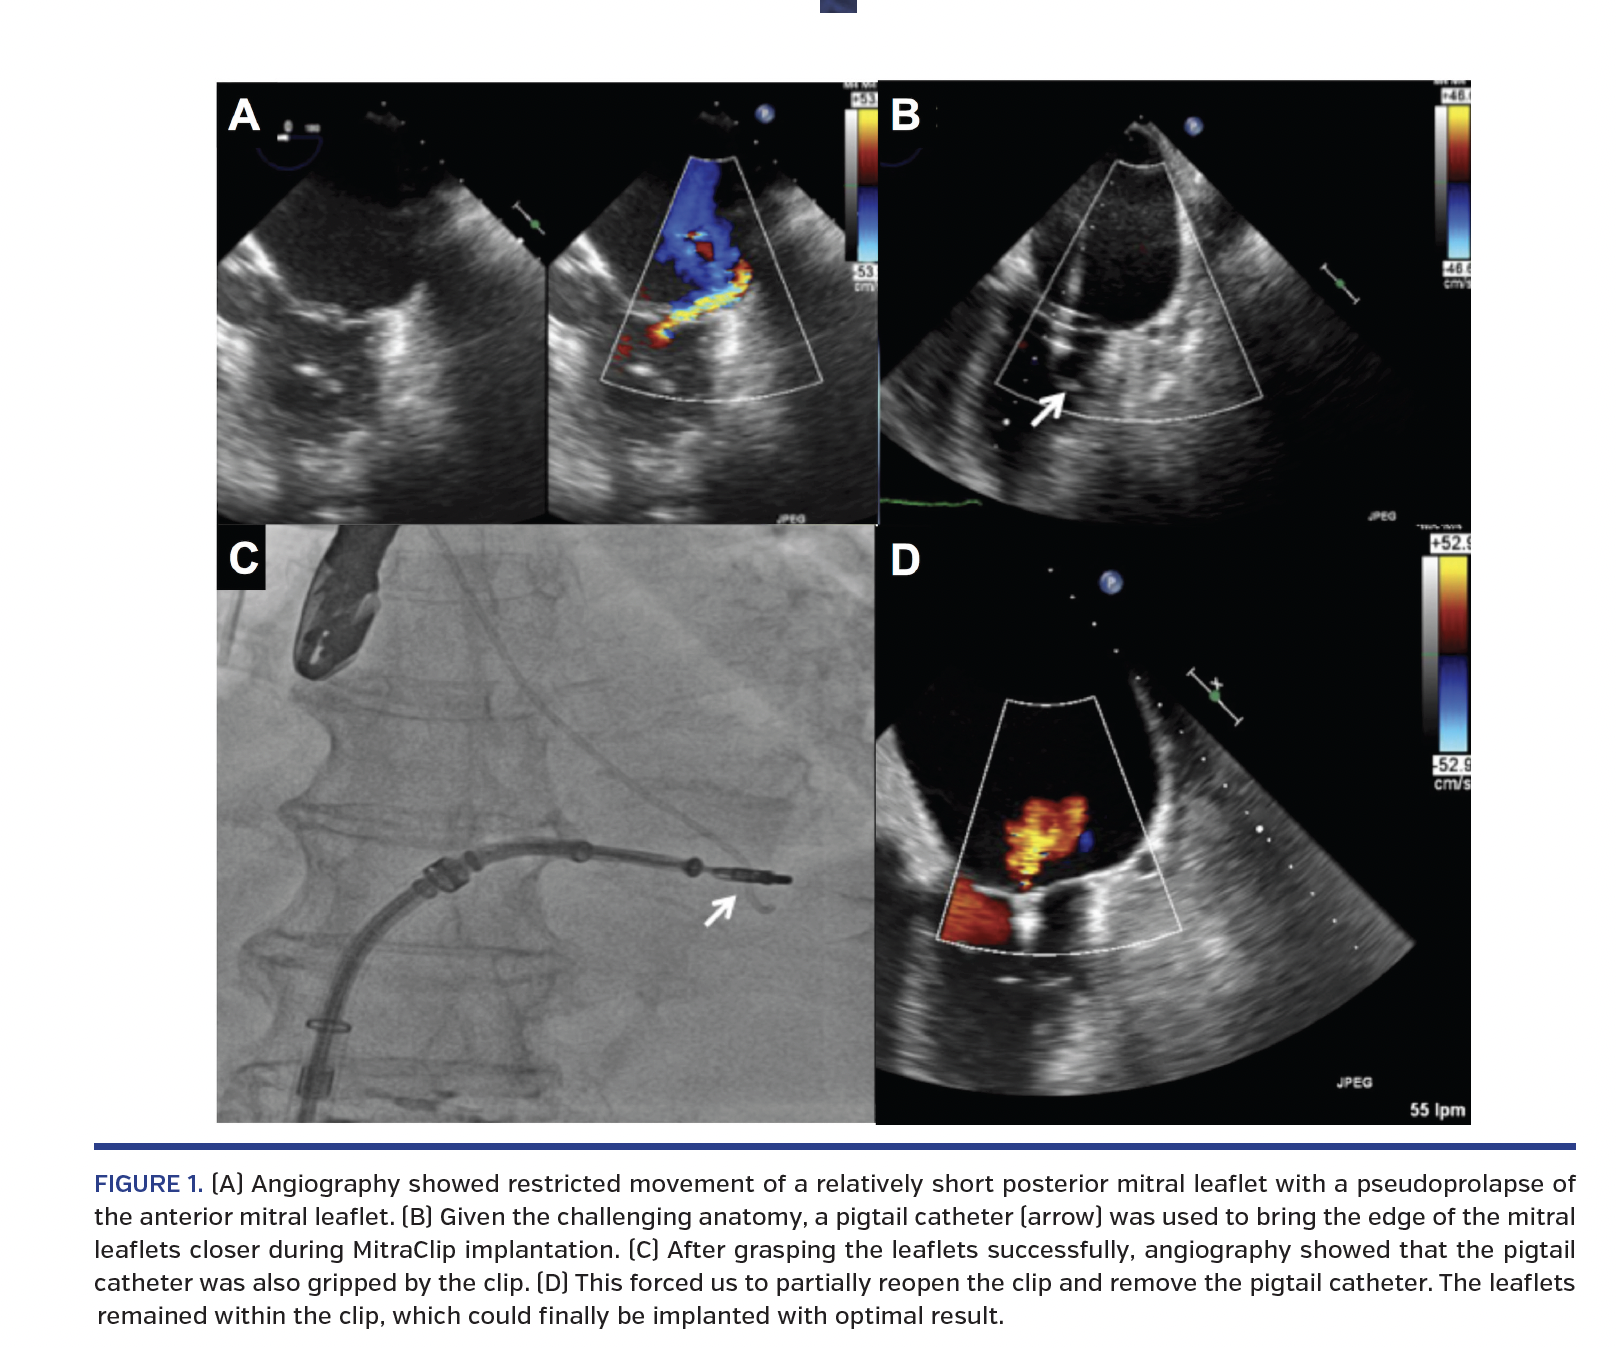

We report the case of an 84-year-old male with past medical history of hypertension and stage 3 chronic kidney disease. In September 2015, he suffered a posterior myocardial infarction with evidence of disease in the right coronary artery and circumflex artery, which were both treated with bare-metal stents in two procedures. In December 2015, he was admitted due to heart failure secondary to severe mitral regurgitation concomitant with severe pulmonary hypertension. The mechanism was the restricted movement of a relatively short posterior mitral leaflet with a pseudoprolapse of the anterior mitral leaflet (Figure 1A; Video 1). The ejection fraction was preserved. MitraClip (Abbott Vascular) implantation was decided due to high risk (logistic EuroScore, 23.12%). Given the challenging anatomy, a pigtail catheter (Figure 1B, arrow) was used to bring the posterior leaflet into closer approximation with the anterior leaflet. After grasping the leaflets successfully, angiography showed that the pigtail catheter was also gripped by the clip (Figure 1C; Videos 2 and 3). This forced us to partially reopen the clip and remove the pigtail catheter (Video 4). The leaflets remained within the clip, which could finally be implanted with optimal result (Figure 1D). Mild regurgitation remained after the procedure (Video 5) and the patient was extubated and discharged with no complications. To date, the patient has remained in New York Heart Association functional class I with no new hospital admissions.